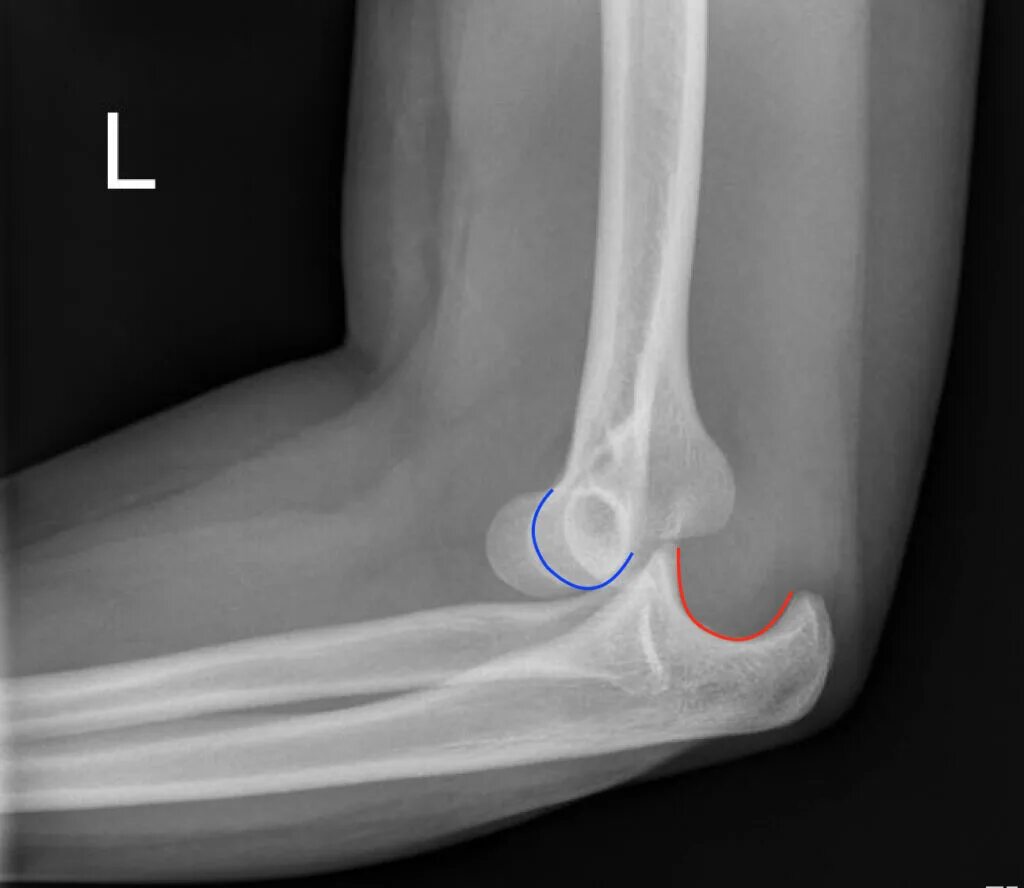

Задний вывих локтевого сустава.

Передний вывих локтевого сустава. вывихи локтевого сустава классификация. положение костей при вывихах в локтевом суставе. наиболее распространенный тип вывиха локтевого сустава.

Вывих локтевого сустава рентген. задний вывих локтевого сустава рентген. подвывих локтевого сустава. подвывих локтевого сустава рентген.

Вывихи локтевого сустава классификация. вывих локтевого сустава кзади. вывихи локтевого сустава травматология. задний вывих локтевого сустава.

Классификация вывихов костей предплечья в локтевом суставе,. задний вывих локтевого сустава рентген. наружный вывих обеих костей предплечья. вправление вывиха локтевого сустава.